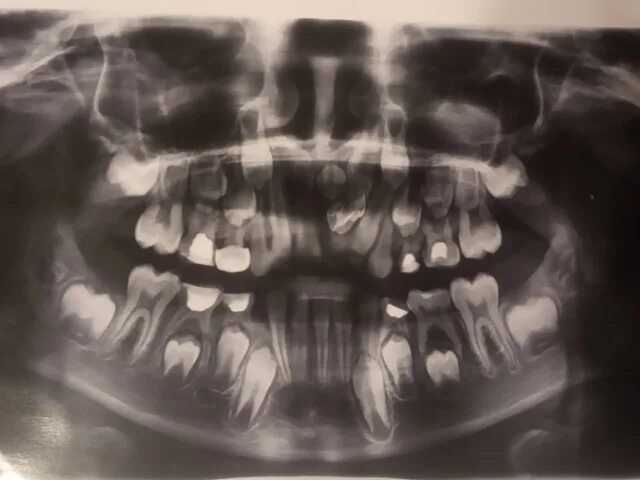

Могут ли быть 9 зубы